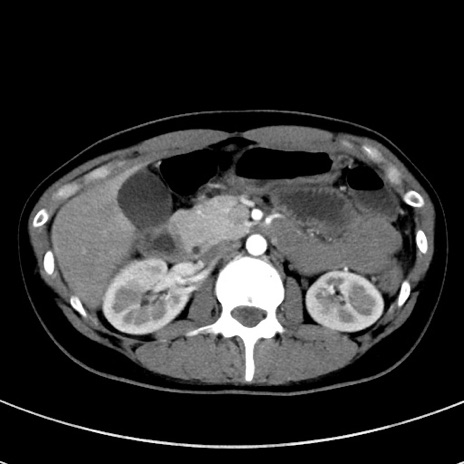

症例17(横断像)

【症例】20歳代女性

【主訴】嘔吐、下腹部痛

【現病歴】昨日夕食後に嘔吐し下腹部痛が出現。本日になっても嘔吐持続し改善しないため来院。

【身体所見】意識清明、BT 37.2℃、BP 108/67mmHg、腹部:平坦、やや硬、下腹部正中から右にかけて圧痛あり、反跳痛軽度あり、tapping pain(+)。

【データ】WBC 13600、CRP 14.94